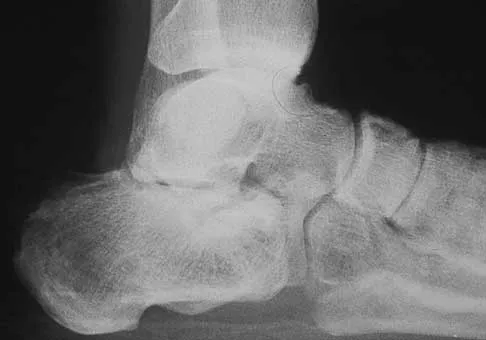

Figures 9a and 9b show the radiographs of a 28-year-old woman who sustained a head injury and a closed injury, without soft-tissue compromise, to her right lower extremity in a motor vehicle accident. Appropriate management of the foot injury should include

The displaced talar neck fracture should be treated with open reduction and internal fixation using screws. Closed reduction and casting will not maintain position, and percutaneous pinning is not able to maintain reduction to allow union. External fixation and amputation are not necessary for this injury unless there is severe soft-tissue loss.